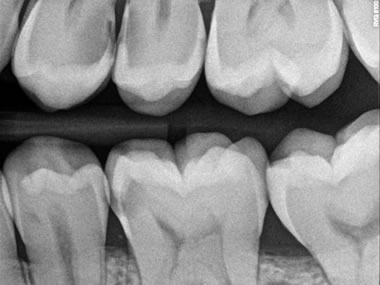

RADIOGRAFIA ENDORALE DIGITALE

La linea del sistema radiografico per immagini digitali della KODAK è un rapido sistema radiografico digitale presente in tutte le 10 postazioni dello studio. In questo modo la diagnosi di patologie del cavo orale viene effettuata immediatamente e può essere simultaneamente valutata da più professionisti in differenti box.